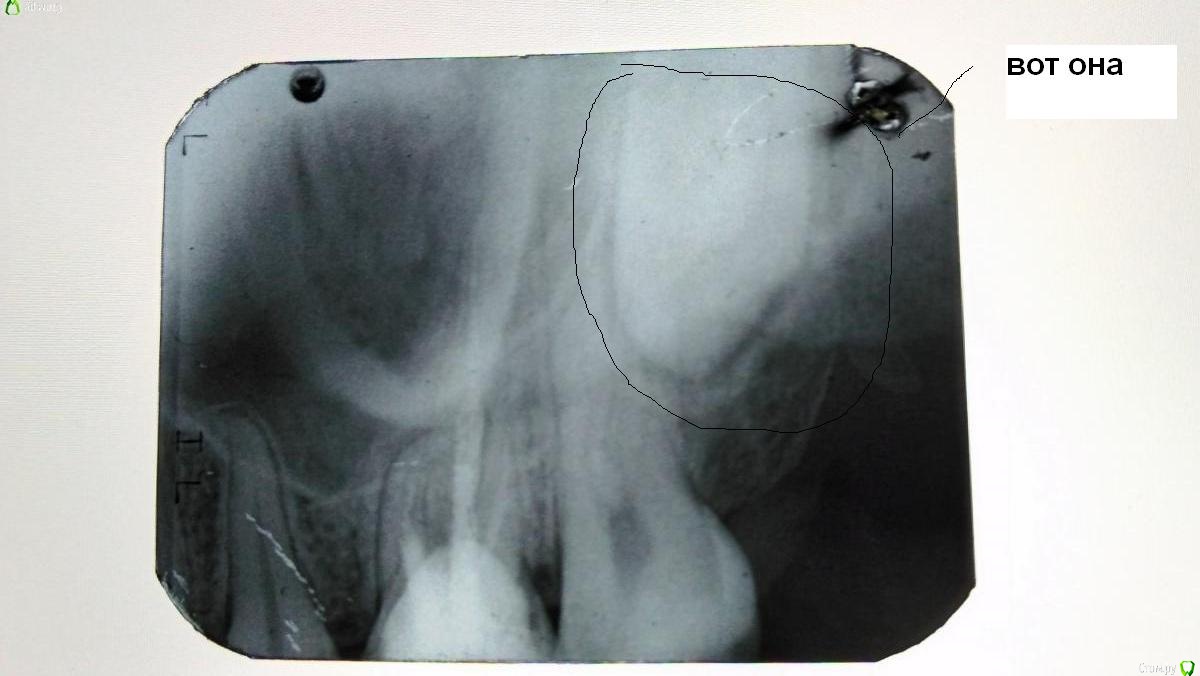

Katerina99 Опубликовано 27 июля, 2017 Поделиться Опубликовано 27 июля, 2017 Добрый день, меня беспокоит верхняя левая шестерка. Сам зуб был пару лет назад депульпирован. Запломбированный зуб иногда меня беспокоил(была боль при смыкании челюстей). Спустя некоторое время стенка зуба треснула и часть этой стенки отпала. Как оказалось позже, под пломбой был кариес. Врач убрал кариозные места и установил штифт. Через пару дней после установки я начала ощущать неприятный привкус во рту, как будто что-то просачивается. Большого внимания этому не уделила. По прошествии месяца с установки штифта я поняла, что этот неприятный привкус идет из-под десны, потому что при промывании десен ирригатором как раз и появлялся этот привкус. В пятницу ходила к врачу. Он постучал чем-то по зубу, но чувствительности абсолютно никакой не было. Да, болеть-то нечему. Боль в районе десны ощущается только при чистке зубов. Сходила сегодня на рентген. Качество снимка так себе, но, может быть, можно что-нибудь понять. И еще вопрос: где моя восьмерка непрорезавшаяся на снимке? Ссылка на комментарий

red_butler Опубликовано 27 июля, 2017 Поделиться Опубликовано 27 июля, 2017 Да, к сожалению качество снимка низкое. Требуется очный осмотр для оценки степени разрушения зуба. Если объем оставшихся твердых тканей позволяет выполнить протезирование, то повторное лечение корневых каналов у эндодонтиста и протезирование зуба искусственной коронкой. Если нет, то удаление зуба. Ссылка на комментарий